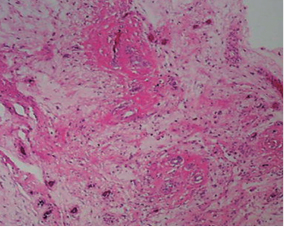

Paciente femenina de 49 años de edad, ama de casa, deportista de alto nivel (realiza tres horas diarias de ejercicios aeróbicos desde hace 10 años). Acudió a rehabilitación el 3 de enero de 2013 por presentar dolor moderado en la zona lateral de la nalga izquierda de tres meses de evolución, manifestado durante la carrera; reportó aumento de volumen de la zona mencionada. A la exploración, se observó aumento de volumen discreto por arriba del trocánter mayor, correspondiendo a masa no dolorosa de consistencia firme, de 5 × 4 cm, fija a planos profundos, dependiendo del músculo glúteo medio por desplazarse con él durante la abducción de la cadera; los arcos de movimiento articular de los miembros pélvicos fueron normales. Al examen clínico muscular: músculos de MI calificados en 5/5 bilateral; reflejos y sensibilidad, normales. Con los datos anteriores, se efectuó el diagnóstico de tumor de tejidos blandos, por lo que se solicitó TAC de abdomen y pelvis, la que mostró presencia de una lesión ocupativa dependiente del músculo glúteo medio izquierdo, con extensión a tejido celular subcutáneo adyacente, con diámetros de 4.7 × 3.8 cm, isodensa, de contornos lobulados bien definidos, con reforzamiento posterior a la administración de contraste endovenoso (Figura 1); abdomen normal. Ultrasonido de la región: se identificó un conglomerado ganglionar en la región inguinal superficial, el mayor con dimensiones de 2.4 cm; este no mostró vascularidad anormal con Doppler color; retroperitoneo sin adenomegalias. Se canalizó a oncología, con el diagnóstico de sarcoma; se le realizó biopsia incisional; se documentó sarcoma fibromixoide y, en un segundo tiempo, se efectuó resección amplia de la lesión. El reporte histopatológico mostró un espécimen irregularmente ovoide que correspondía a músculo estriado, con dimensiones de 4.5 cm de eje principal, fibroso y de color rojizo; microscópicamente, proliferación de células redondas y ovoides de manera difusa con patrón mixoide, que carecían de atipias y mitosis, alternando con sitios que constituían nódulos, que contenían células redondas dispuestas en hileras con abundantes haces de colágena hialina; las células proliferantes tenían citoplasma pálido y, en algunos sitios, eosinófilo; su núcleo era grande, nucléolos prominentes; en escasos sitios, las células mencionadas mostraban el núcleo lobulado e hipercromático y mitosis promedio de cinco por cada 20 campos a seco fuerte; en cortes de la zona periférica se identificó colágena hialina que contenía trabéculas de hueso metaplásico. Los bordes de sección quirúrgica, libres de actividad neoplásica; con diagnóstico de sarcoma fibromixoide de grado histológico bajo (Figura 2). El estudio inmunohistoquímico mostró CD-10, enolasa neuroespecífica y proteína S-100 negativas, con vimentina positiva, lo que apoyó el diagnóstico de sarcoma fibromixoide de los tejidos blandos. En ese momento, se catalogó en estadio IA (T1bN0M0).

Figura 2: Corte histológico que muestra células redondas y ovoides que proliferan de manera difusa con patrón mixoide, carecen de atipia y mitosis, alternando con abundantes haces de colágena hialina. La inmunohistoquímica mostró vimentina positiva y proteína S100 negativa. Diagnóstico histológico: sarcoma fibromixoide de bajo grado.